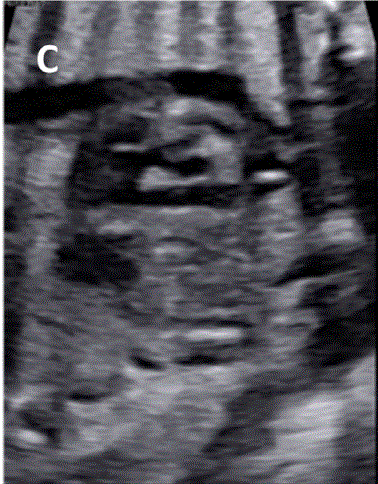

图29胎儿Ebstein异常和TV发育不良。(A)在该胎儿中,严重的三尖瓣反流与进行性心脏增大有关,尤其是右心房(RA)扩张,如这些在19周和34周时的系列图像所示,并且可能与心力衰竭/水肿的演变有关。(B-D)四腔切面中胎儿严重Ebstein异常显示严重心脏扩大的图像。(C)从矢状切面可见广泛的三尖瓣反流(箭头),由于室间隔瓣叶移位,反流起源于TV瓣环下方,甚至向 RV 流出道射流。彩色多普勒和 CW 多普勒显示也有连续的肺动脉反流。(D) 后一项发现表明,右心室无法产生足够的压力来打开肺动脉瓣